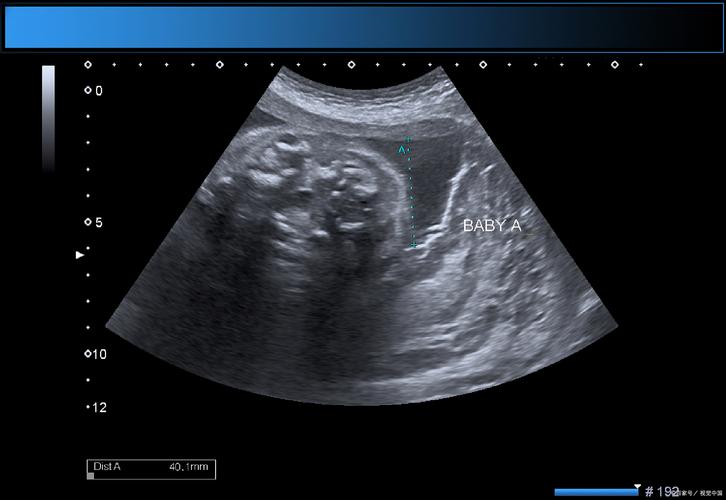

(图片来源网络,侵删) -